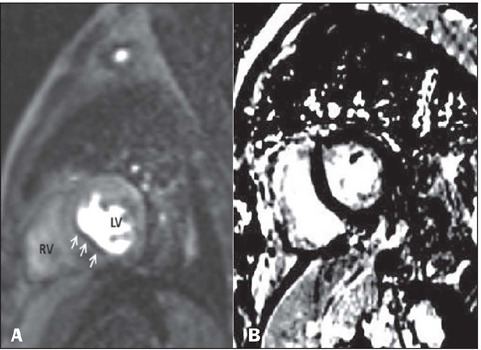

Results: Pathological results were seen in six (30%) of the patients in our study sample. Scar tissue was identified as a high-risk factor in three patients (15%), and myocardial hibernation was shown to pose a moderate risk in three patients (15%). In the remaining 14 cases, no pathology was identified, and the risk was therefore categorized as low. A statistically significant disparity in mortality rates was observed between the high- and low-risk groups (p < 0.05). There were no statistically significant differences between the two groups in terms of the ECG and cardiac biomarkers.

Conclusion: Our findings indicate that CMRI is effective in accurately categorizing risk groups and detecting ischemic conditions, even when such events are not evident on ECG or laboratory tests.

Abstract Image